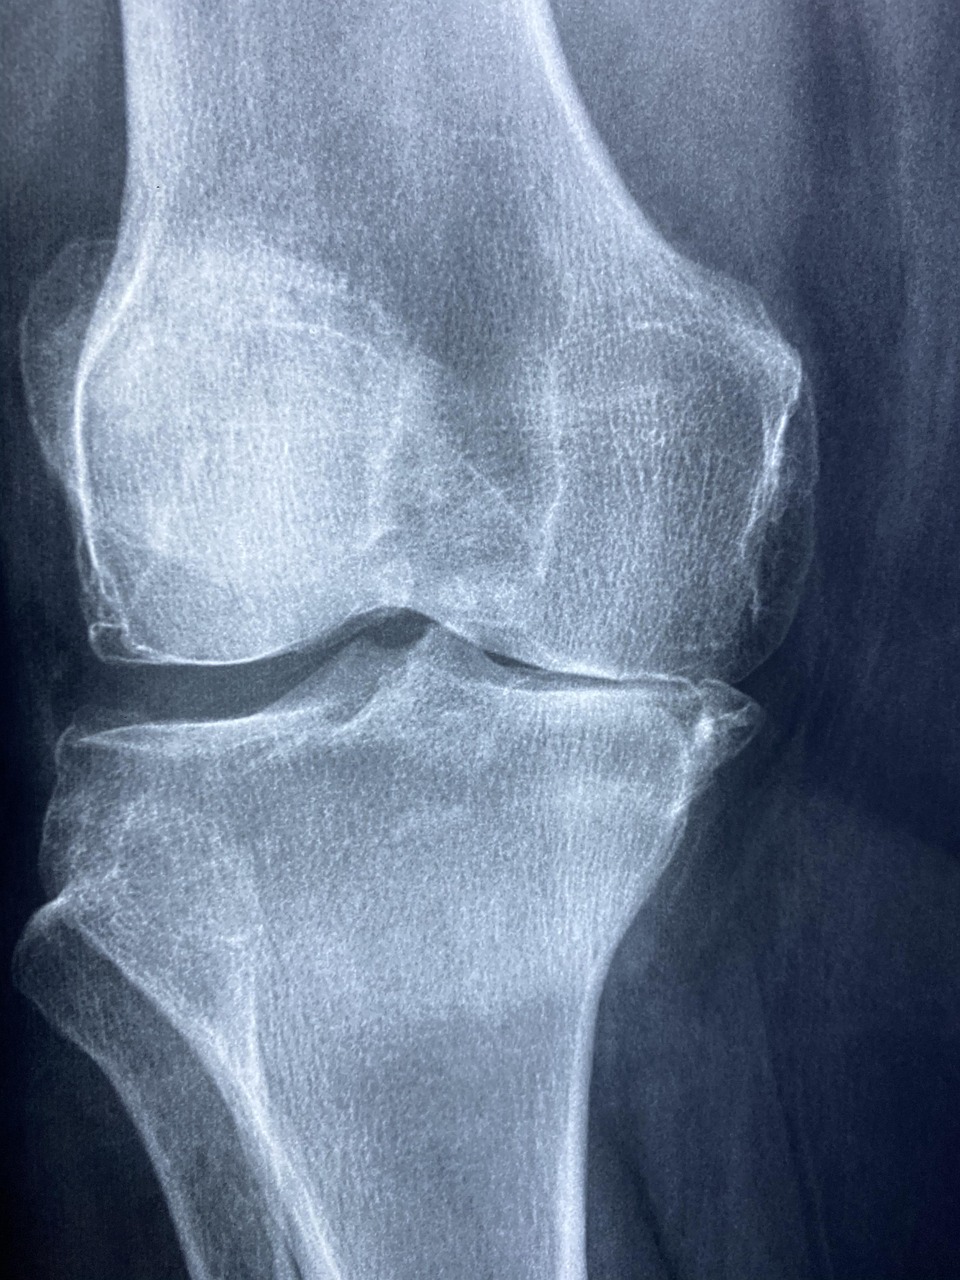

퇴행성 관절염 초기 증상|이럴 땐 병원 가야 하나요?

무릎이나 손가락 관절이 뻣뻣하고, 아침에 일어날 때 잘 움직여지지 않으시나요?

특히 계단 오를 때 무릎이 시큰하거나 걸을 때 뚝뚝 소리가 난다면 퇴행성 관절염 초기 증상일 수 있습니다.

⚠ 퇴행성 관절염 초기 증상 5가지

- 1. 관절 뻣뻣함 – 특히 아침에 일시적으로 굳어 있음

- 2. 무릎 통증 – 무리하거나 장시간 움직였을 때 통증 증가

- 3. 관절 부종 – 무릎이나 손가락이 붓고 열감 있음

- 4. 움직일 때 소리 – 관절에서 ‘뚝’, ‘딱’ 소리가 반복됨

- 5. 무릎 안쪽 통증 – 체중을 실을 때 유독 불편